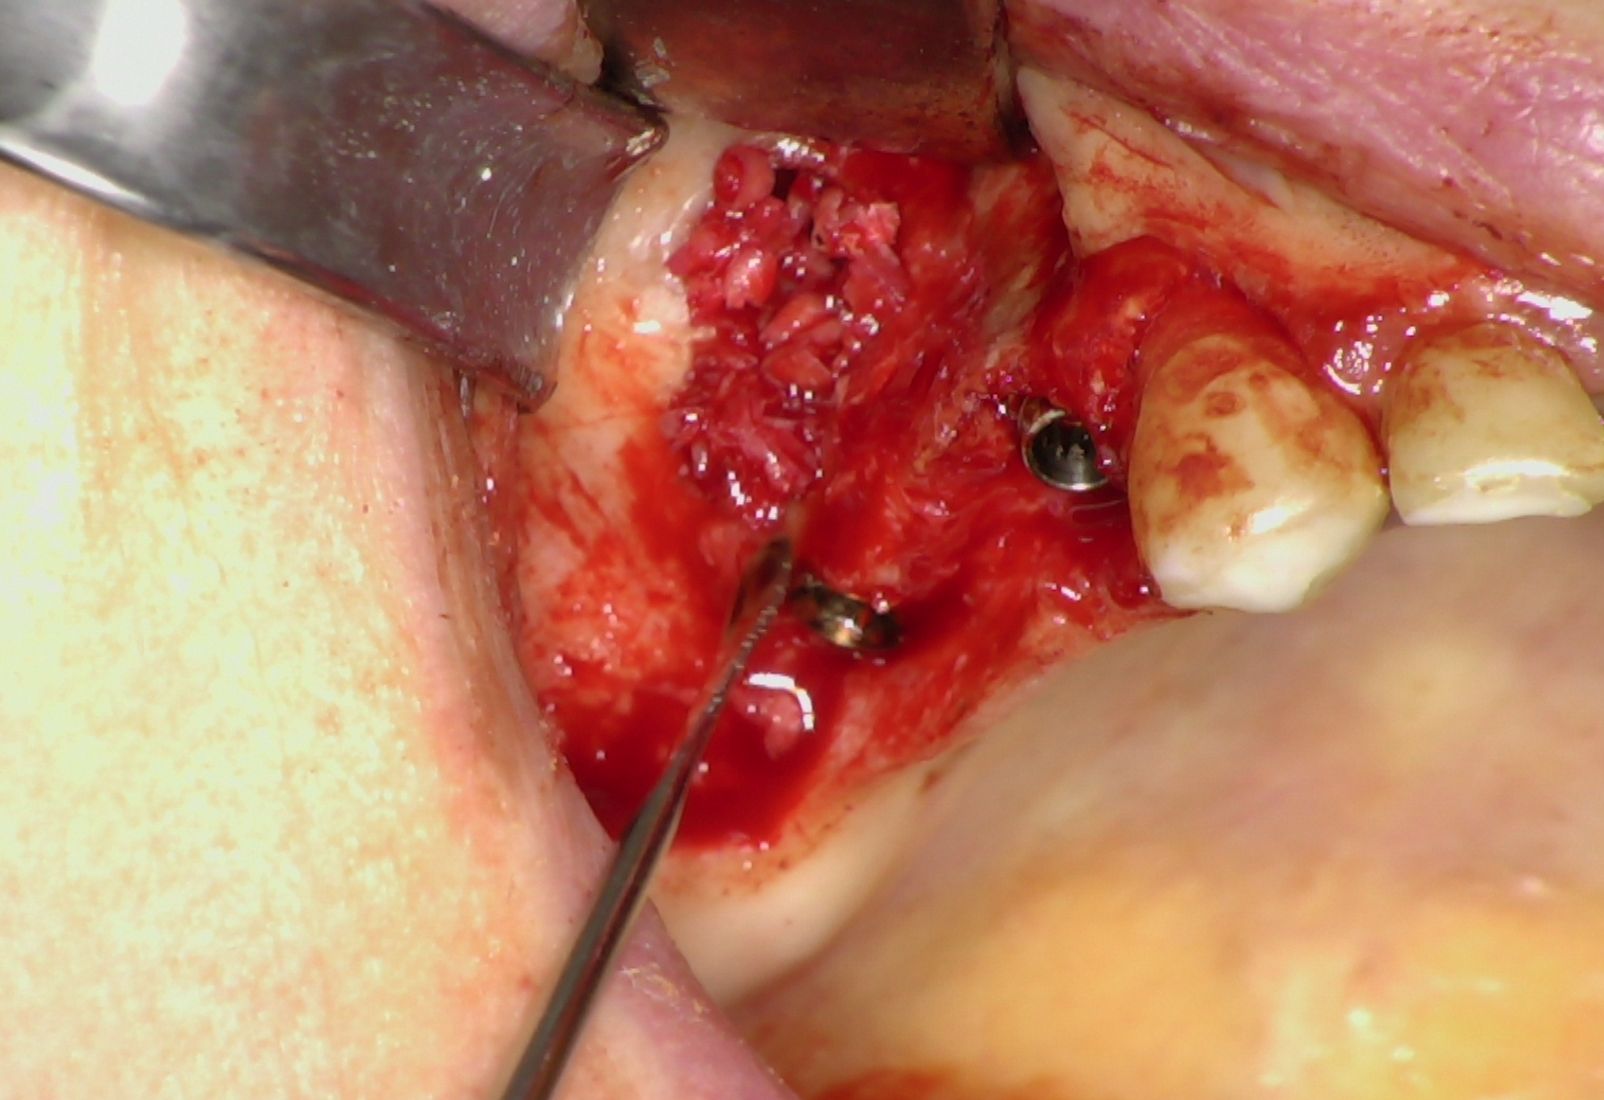

Nei settori posteriori, caratterizzati da significativa atrofia ossea e da pneumatizzazione del seno mascellare, è stato adottato un approccio transinusale. È stata pertanto realizzata una finestra laterale per consentire il sollevamento della membrana di Schneider (Fig. 3), procedura eseguita con particolare attenzione per preservarne l’integrità. Successivamente i siti implantari sono stati preparati con una traiettoria inclinata che attraversa la cavità sinusale, permettendo l'ancoraggio nell'osso basale anteriore. Sono stati quindi inseriti due impianti BT-Rhyno (Fig. 4), progettati specificatamente per l'inserimento transinusale e in grado di garantire adeguata stabilità anche in presenza di ridotto spessore osseo crestale.

Fig. 3 - Membrana di Schneider

Al termine della fase implantare è stata eseguita una rigenerazione ossea localizzata intorno agli impianti posteriori utilizzando osso autologo prelevato mediante bone scraper (Fig. 5). Questo passaggio ha consentito di colmare eventuali spazi peri-implantari, favorendo i processi di osteointegrazione e contribuendo a migliorare la prognosi a lungo termine.

Fig. 5 - Osso autologo